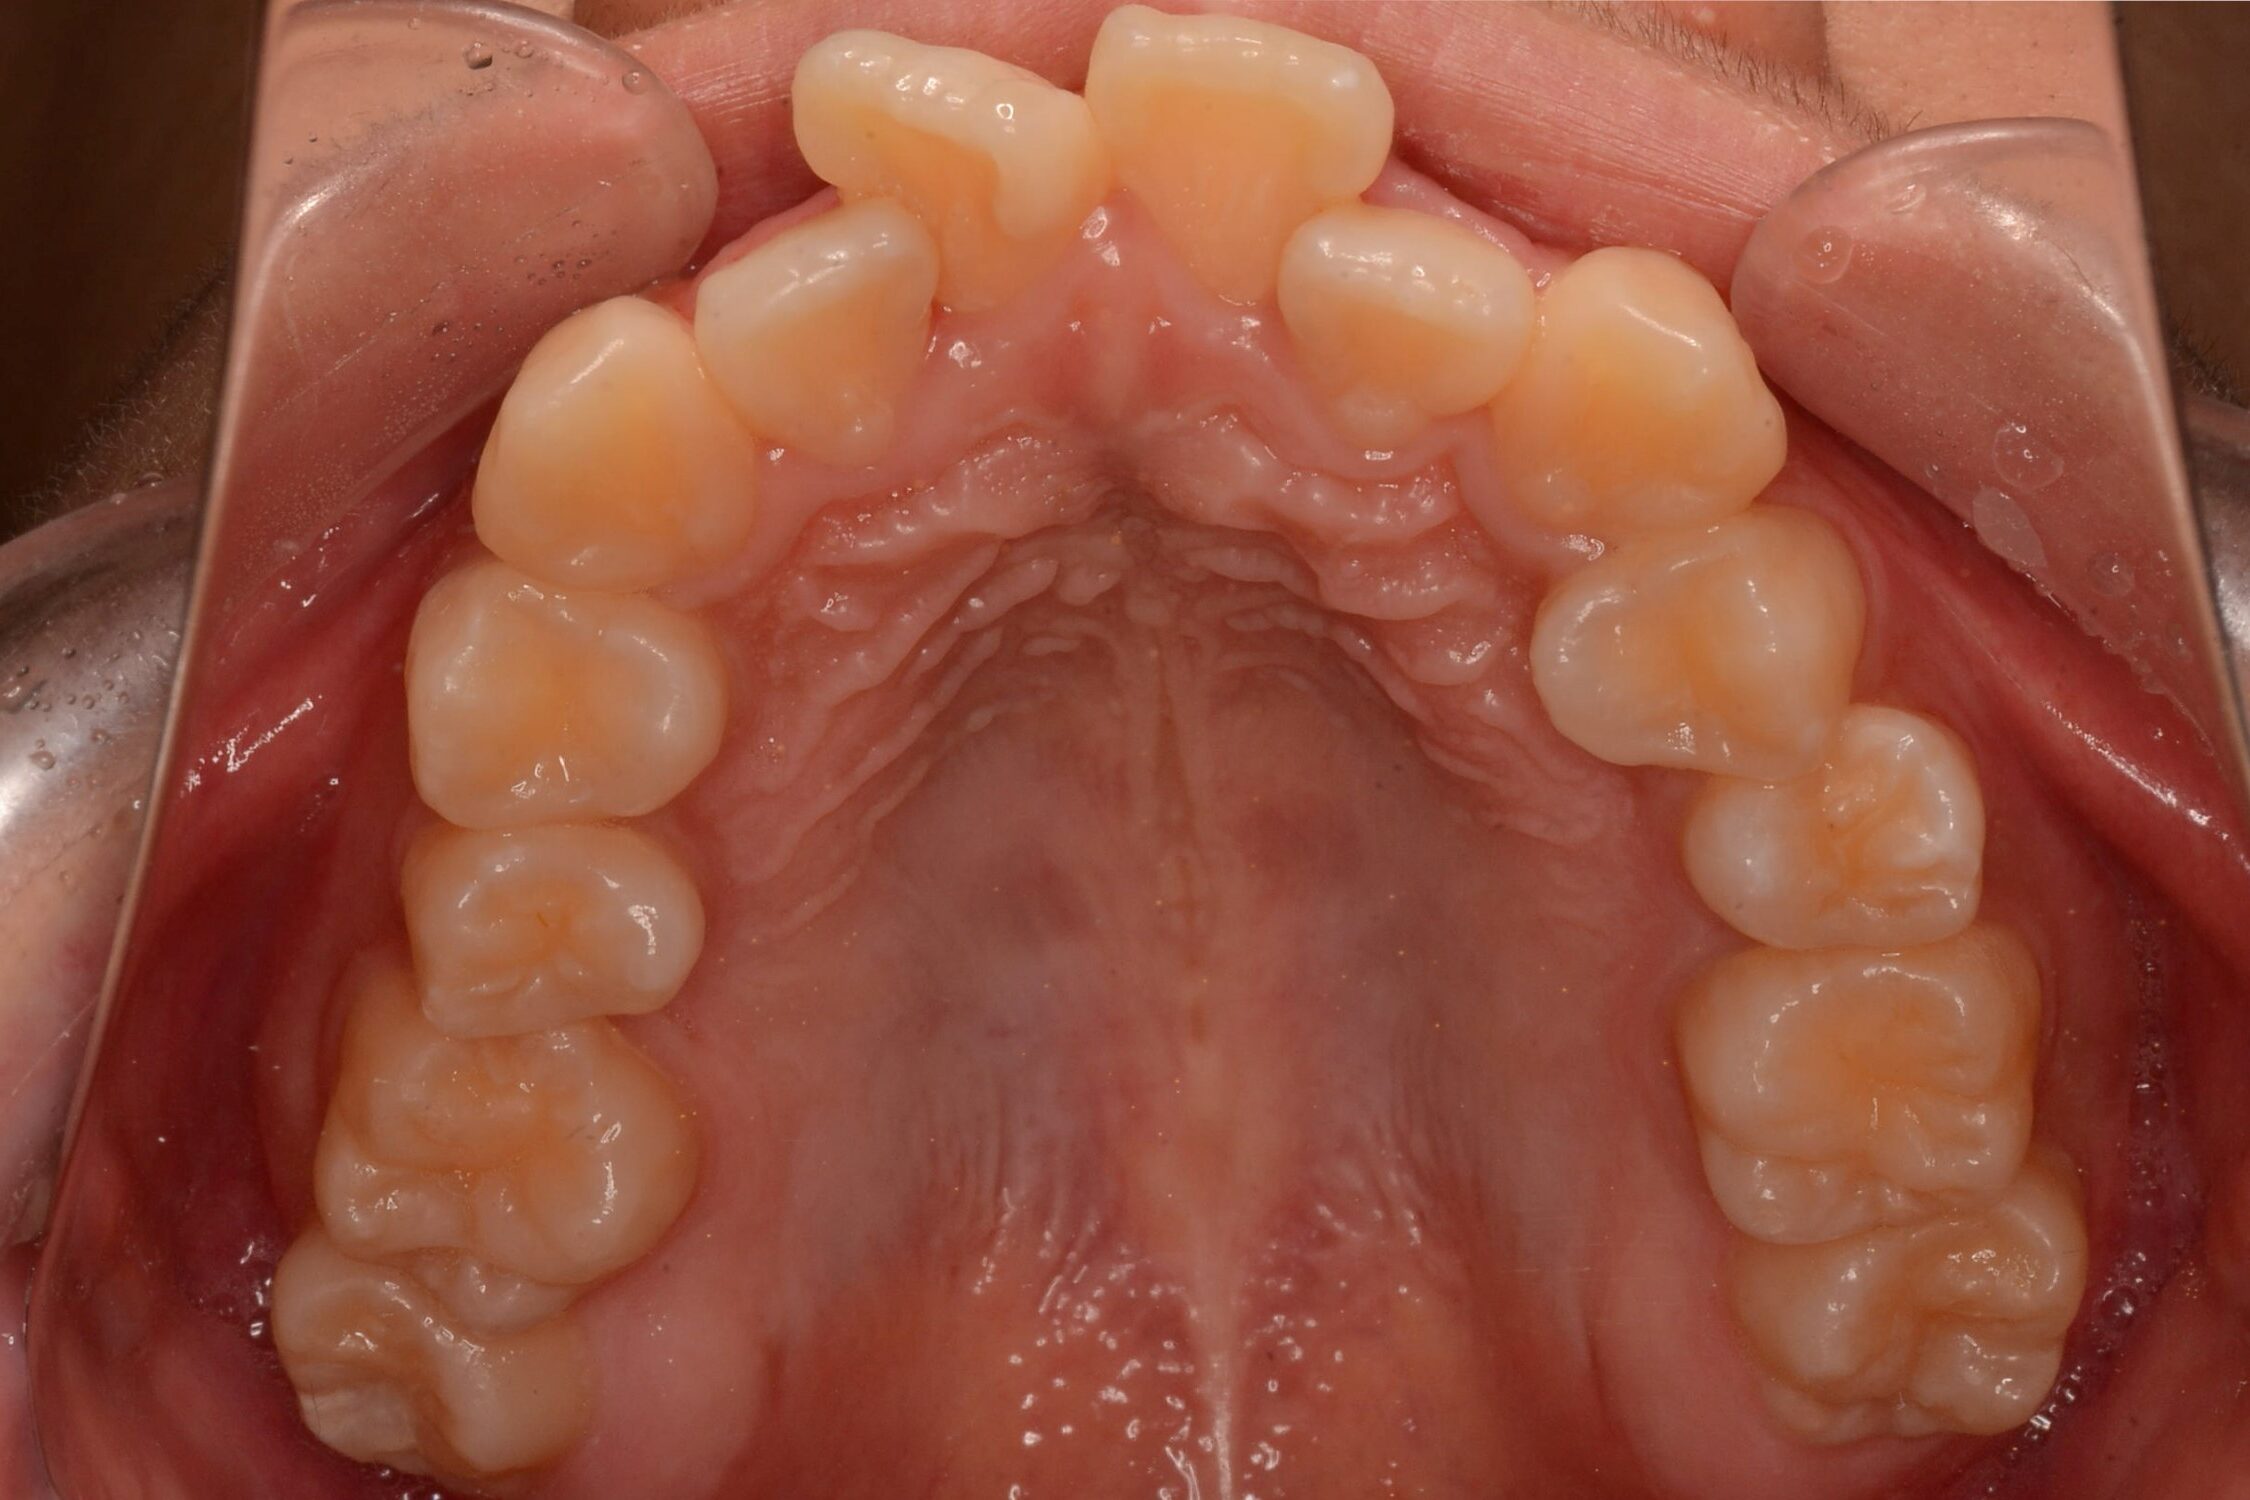

症例2:八重歯が気になる

| 患者様データ | 20代 女性 |

| 来院主訴 | 八重歯が気になる。 |

| 治療内容 | 八重歯を治すために上の親知らずを抜歯し、インビザラインにてマウスピース矯正を開始しました。かみ合わせを整えるためにゴムかけを行いました。 |

| 概算治療費 | 約85万円 |

| 治療期間 | 1年3ヶ月 |

| 通院回数 | 8回 |